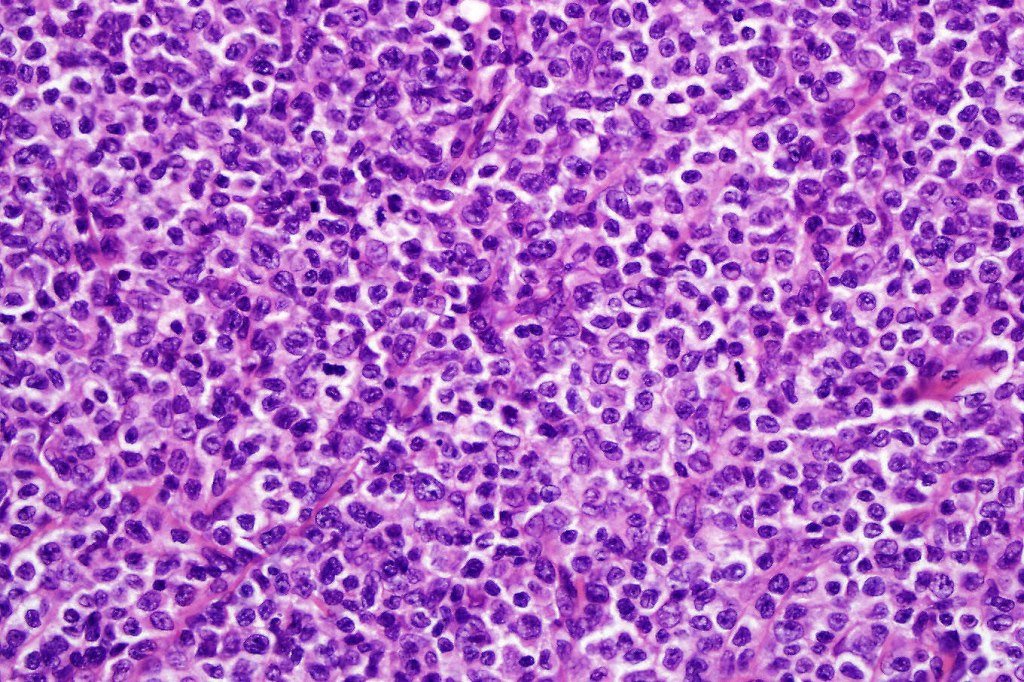

Histological features

The histological hallmark of mycosis fungoides is the presence of large atypical lymphocytes with a convoluted/cerebriform nuclear border (Sézary cells). These may be found at the epidermal-dermal jnuction and as collections within the epidermis (Pautrier microabscess). These are most easily found in plaque stage disease. The epidermal component can be subtle in patch stage disease and is often lost in tumor stage dsease. The classification into patch, plaque & tumor stage disease is less helpful histologically as the features merge from one to the other. It is all a matter of degree.

Plaque Stage Disease

•Compact hyperkeratosis & patchy parakeratosis

•Acanthosis

•Psoriasiform hyperplasia common

•Epidermotropism is often marked with conspicuous Pautrier microabscesses

•Lichenoid variant & poikiloderma atrophicans vasculare

•Variable folliculotropism (+/- mucinosis) & syringotropism

•Coarse collagen bundles in papillary dermis

•Superficial band-like dermal infiltrate of atypical lymphocytes, eosinophils, plasma cells & histiocytes